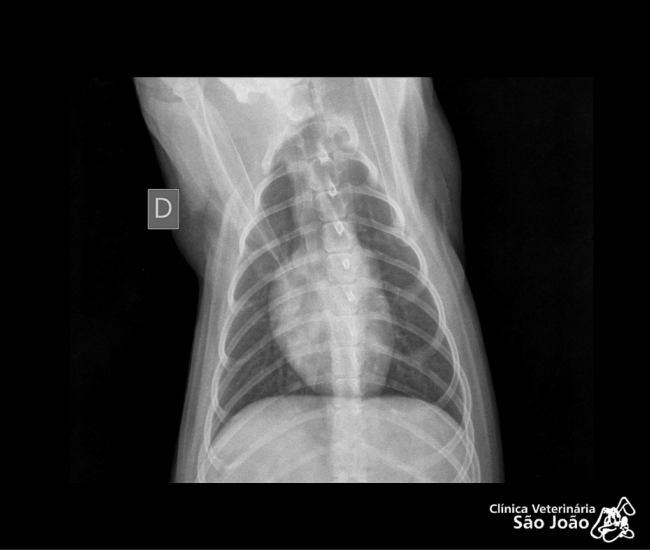

- Diferentemente do raio-x analógico, este raio-x oferece altíssima definição e todas as vantagens da tecnologia digital. É possível aproximar a imagem, trabalhar o contraste, exposição.O software permite ainda avaliações da medida cardíaca do animal e graus de displasia coxofemoral, por exemplo – explica o Dr. Nardeli Lucena.

- sofware com medidas para avaliações do tamanho cardíaco e medições dos ângulos de Norberg para diagnóstico e classificação de displasias coxofemorais;